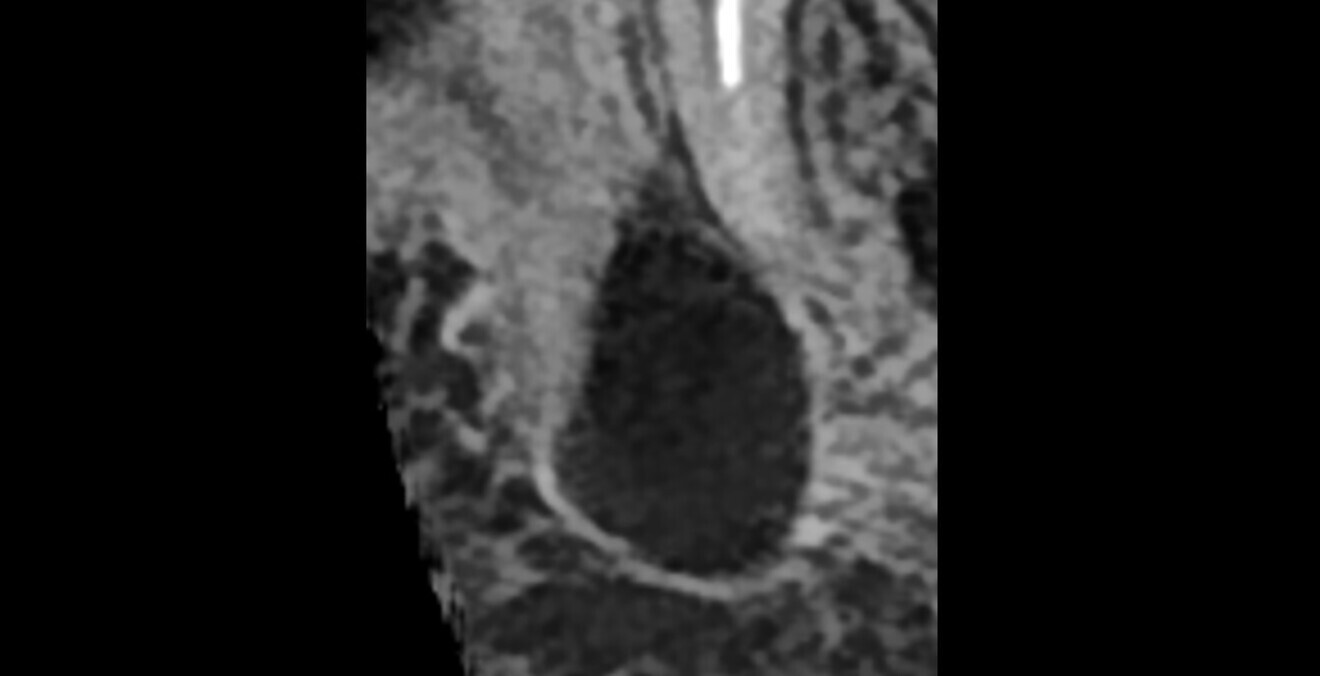

In this first case, the patient, who lived abroad and was unable to travel at the time, had swelling of her right mandible (Fig. 6), had had breast cancer and had been under bisphosphonate treatment for 18 months. She sent a panoramic radiograph (Fig. 7), and this showed a minor apical infection of the mandibular right first molar, which had undergone endodontic treatment. A CBCT scan was then taken, and from examining her scan, we could clearly see an area of bone densification (Fig. 8). This should be a red flag because this indicates the start of bone necrosis.

Fig. 8: Axial view of the CBCT scan showing a small apical infection of the mandibular right first molar, surrounded by an area of dense ossification extending over a large part of her mandible.